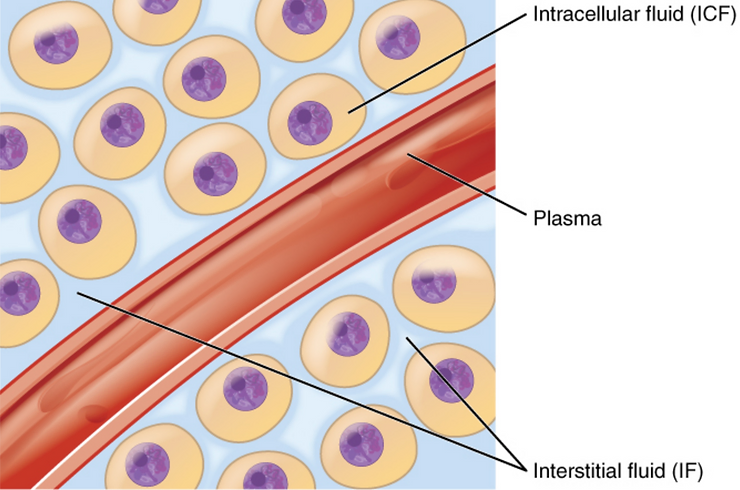

Decompensated acidosis of the body fluids causes erythrocytic or red blood cell membrane degeneration and genetic mutation causing the conditions of rouleau, membrane degeneration causing the spiking or knobing or ‘Corona Effect’, acanthocytosis, erythrocytic symplastism or red blood cell clotting, thrombosis and disseminated intravascular coagulation (DIC). There are at least eight major contributing toxic factors that cause the increased levels of acidity in the body fluids leading to a significant decline in the alkaline design of the major body fluids (See Illustration 2: Interstitial fluids of the Interstitium organ, the intravascular fluids and the Intracellular fluids) from their ideal pH of 7.365 to an unhealthy pH of 7.265 to 7.165.

In addition, we used our unique patent-pending non-invasive 3-D Bio-electro-scanning and non-invasive intravascular blood testing devices for testing and quantifying the biochemistry, including the pH of the intracellular fluids, the intravascular fluids and the interstitial fluids of the Interstitium, the largest organ of the human body. By measuring and comparing the biochemistry of all the body fluids it became clear that patients who tested positive for pathological blood coagulation or disseminated intravascular coagulation and positive SARS-CoV antibodies were all in decompensated acidosis of the interstitial fluids, including the interstitial fluids of the lungs leading to the genesis of oxygen deprivation, hypoxia and sudden death was not viral, bacterial or fungal.[33][34][35]

After testing the body fluids of thousands of patients over the last seven years exhibiting pathological blood coagulation (DIC) we have concluded that the cause of oxygen deprivation of blood and lungs, red blood cell degeneration, DIC, thrombosis, hypoxia, severe acute respiratory syndrome or SARS-CoV and sudden death is due to decompensated acidosis of the intravascular fluids and the interstitial fluids of the Interstitium organ.[32]